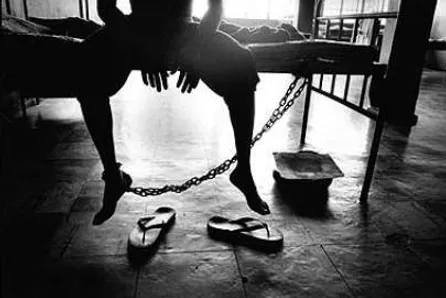

La sveglia non ha suonato, mi devo sbrigare! Metto la macchinetta del caffè sul fuoco e intanto scelgo i vestiti da indossare, faccio colazione e poi subito sotto la doccia. Esco dal bagno, mi asciugo, mi vesto, controllo di aver preso tutto, cellulare, portafoglio, chiavi, sì ok c’è tutto! Esco, chiudo la porta di casa con entrambe le mandate e…l’ho chiuso il gas?? Nella vita quotidiana è plausibile incorrere in dubbi circa la validità delle proprie azioni (verificare ad esempio due volte di aver chiuso la porta di casa e di incorrere nuovamente nel dubbio dopo averlo fatto): questo, fortunatamente, non accade sempre, visto che il nostro cervello effettua, al di fuori della coscienza, dei controlli costanti che ci garantiscono la sicurezza. La caratteristica principale di coloro che sono affetti da disturbo ossessivo compulsivo (DOC) riguarda invece l’alterazione di tale processo, che non consente loro di “raggiungere la conclusione logica delle proprie azioni”. Il DOC è una sindrome caratterizzata da ossessioni e compulsioni che durano almeno un’ora al giorno ed hanno un’entità tale da interferire col normale funzionamento della persona nella vita quotidiana. Le ossessioni sono vissute sotto forma di pensieri, impulsi o immagini intrusivi che provocano un marcato stato d’ansia e disagio; le compulsioni sono atti mentali o comportamenti ripetitivi che la persona è obbligata a mettere in atto per alleviare l’ansia provocata dalle ossessioni.